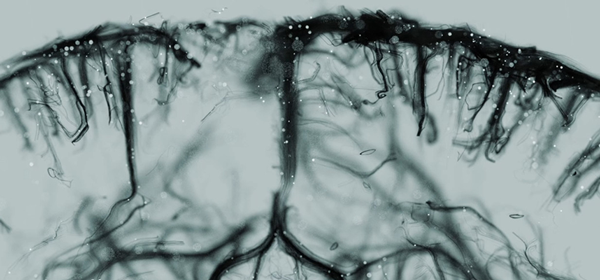

Organs are supplied by a complex network of blood vessels, which are essential for their proper functioning. Some imaging techniques give a global view of this vascular network, but for the first time, ultrafast 3D imaging allows us to observe blood flow from the large arteries to the smallest blood vessels of only a few micrometres in diameter.

For several years, the Physics for Medicine Paris laboratory has been a world leader in non-invasive, non-ionizing ultrasound imaging. The laboratory has made major advances in vascular imaging over the last ten years, with the development of ultrasensitive Doppler imaging (uDoppler) and then ultrasound localisation microscopy (ULM) in 2D. The technology is licensed to the company Iconeus (a start-up resulting from the laboratory’s work) in the field of brain imaging, where it already has numerous applications in neuroscience research. Researchers at PhysMed have just reached a major milestone by deploying ULM in 3D: thanks to the three-dimensional aspect, the researchers obtained super-resolved images of the rodent heart and brain, at the scale of the entire organ.

To achieve such a feat at such fine resolutions, the scientists inject microscopic gas bubbles, the position of which is monitored at high imaging rates. This makes it possible to obtain detailed information on blood flow and channel size, and thus to reconstruct the entire vascular activity of the organ. In addition to providing fundamental knowledge of organ function, this technique could also provide valuable information on various cardiovascular pathologies and even measure the effectiveness of different treatments.